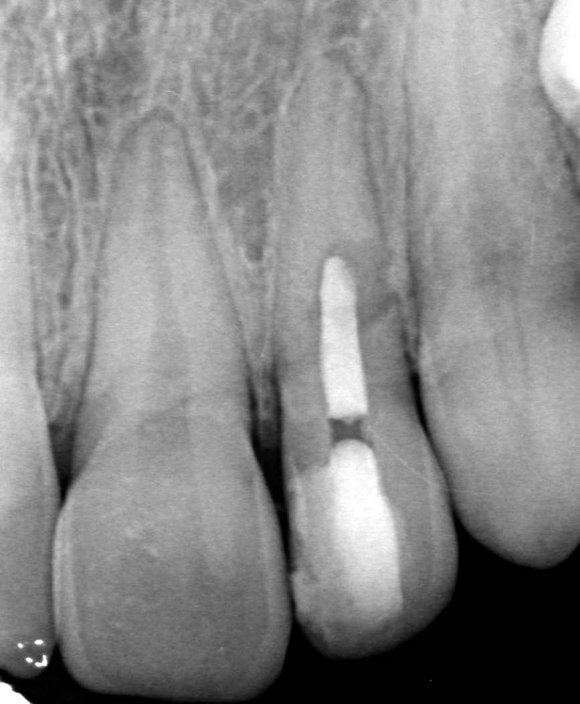

Also, there were signs in favor of internal resorption. The defect was below the cervical part, which is not typical of external cervical resorption. The response to cold stimuli reduced, which is not characteristic of external resorption, as it affects the pulp only in the last stages of tooth structures decay. Furthermore, the X-ray obliteration of the root canal beyond the resorption area is not characteristic of external resorption. Visit 1: Pre-op X-ray plus anesthesia with sol. Ubisthesini 4% -1 ml, isolation with rubberdam. The access was made as close as possible to the incisal edge. When opened, at first glance the pulp chamber looked quite II.

The patient started orthodontic treatment, however, tooth 2.2 was temporarily not included in the orthodontic therapy at the endodontist's request, who was willing to observe it for a year. Furthermore, increased resorption could have been provoked. As of today, the tooth is included in the orthodontic treatment and is being followed up.

In eighteen-month time, the stabilized process is observed, meaning that the diagnosis has been correct and the manual work has been performed without problems. No complaints are observed.